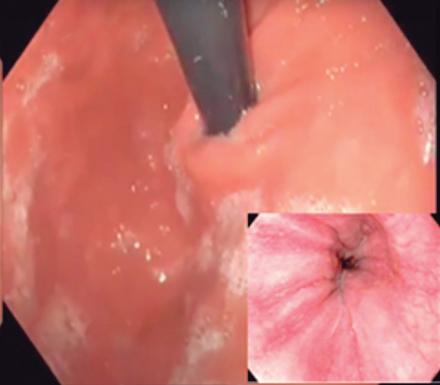

CASOS CLÍNICOS Biopsia guiada por ecoendoscopía como herramienta diagnóstica mínimamente invasiva para metástasis mesorrectal de carcinoma de células claras renales: reporte de caso

Nicole Marie Kahn, Mayra Florencia Defanti, Yanina Gabriela Carlino